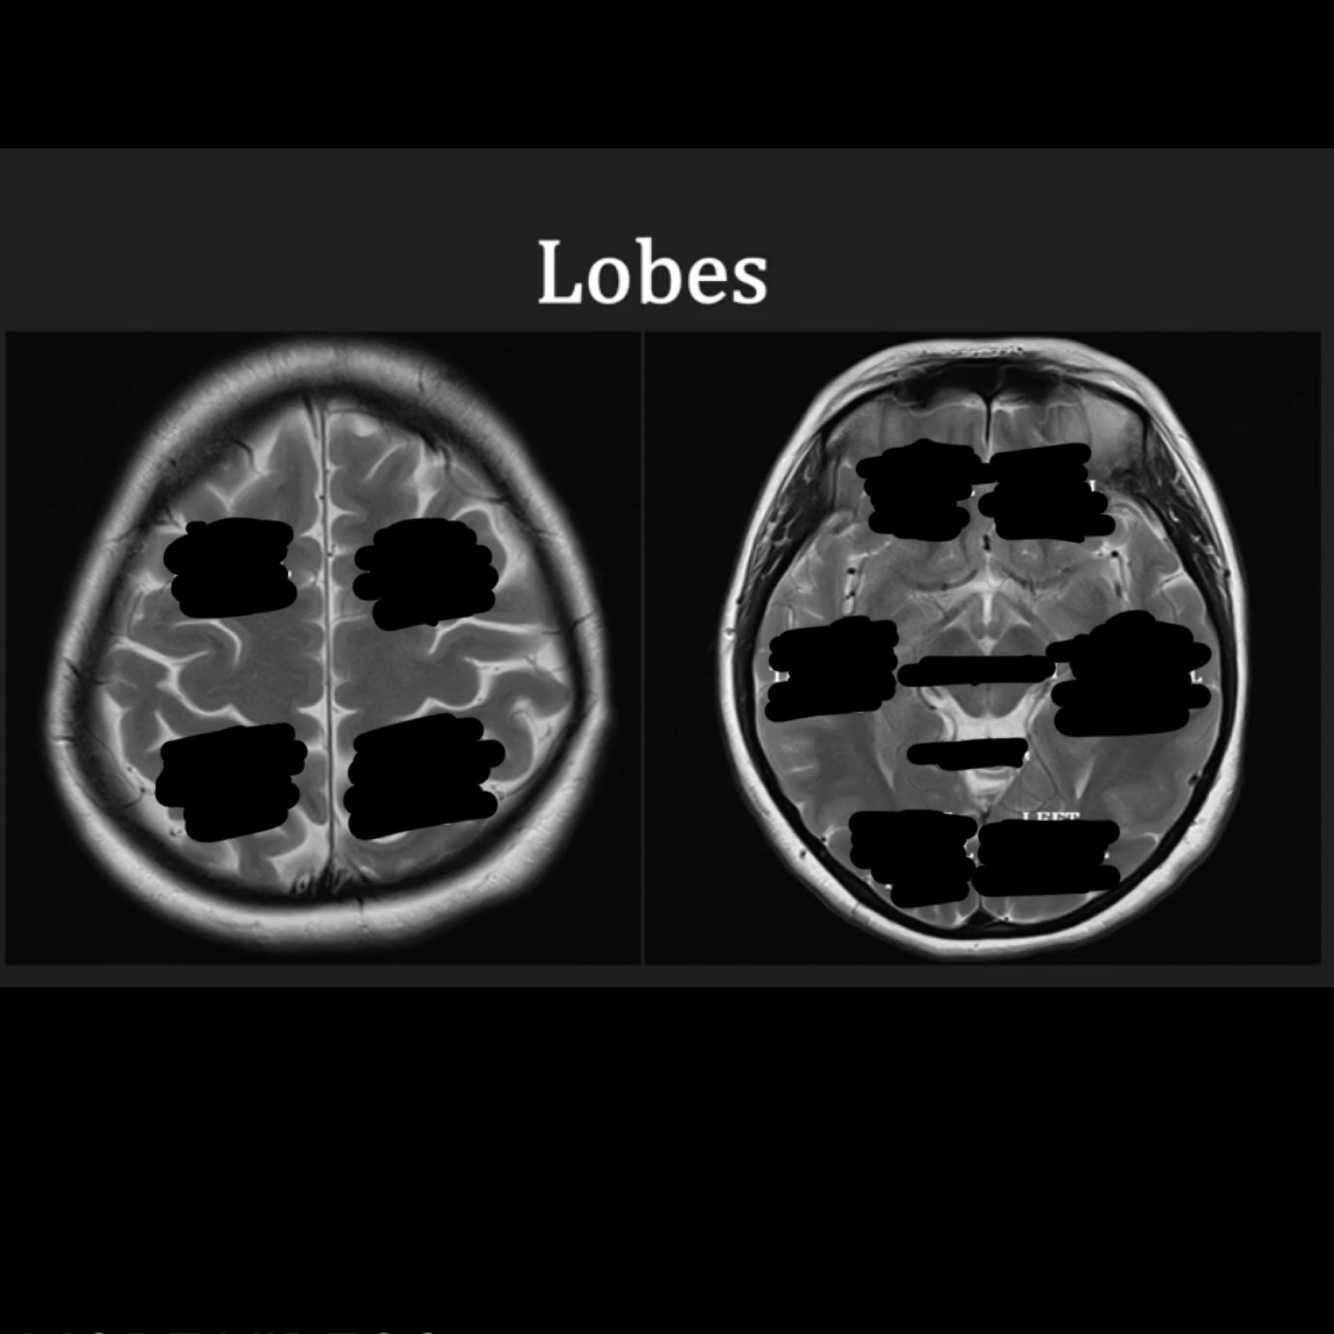

12

Q

Anatomical lobes of the brain, brainstem and cerebellum

A